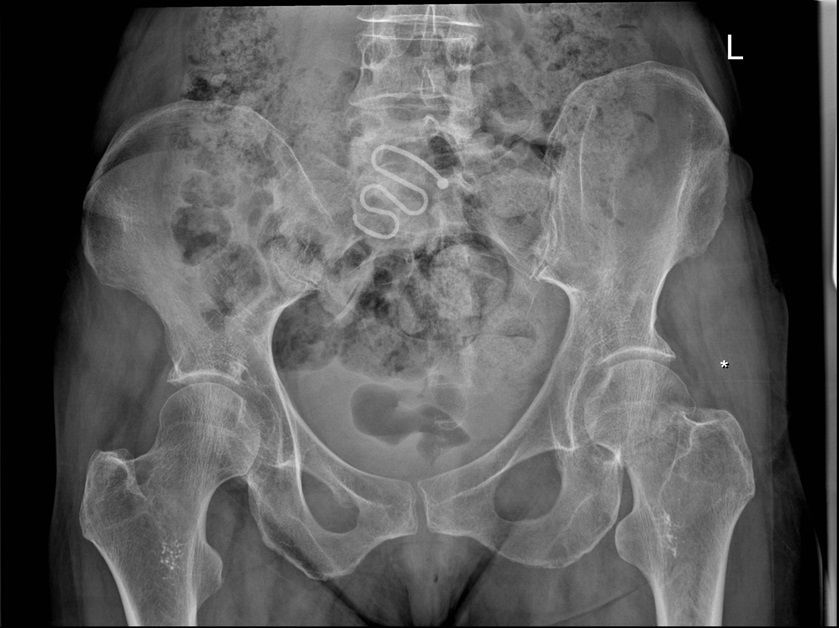

Question 3

Question

Which operation would you perform?

Answer

• THR

• Hemiarthroplasty